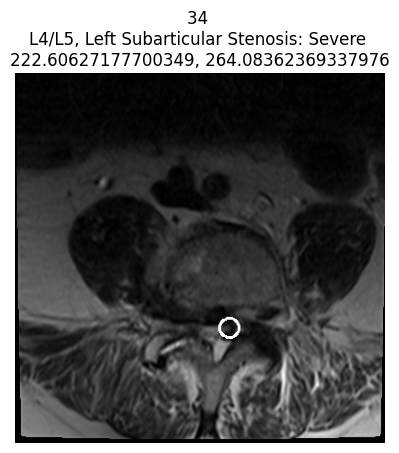

coor_entries = df_coor[df_coor['study_id'] == int(patient['study_id'])]

print("Chỉ hiển thị các trường hợp nặng (Severe) cho bệnh nhân này")

for idc, c in coor_entries.iterrows():

for i in im_list_dcm[str(c['series_id'])]['images']:

if int(i['SOPInstanceUID']) == int(c['instance_number']):

try:

patient_severity = patient[

f"{c['condition'].lower().replace(' ', '_')}_{c['level'].lower().replace('/', '_')}"

]

except Exception as e:

patient_severity = "unknown severity"

title = f"{i['SOPInstanceUID']} \n{c['level']}, {c['condition']}: {patient_severity} \n{c['x']}, {c['y']}"

if patient_severity == 'Severe':

display_coor_on_img(c, i, title)

- Lọc ra tất cả các vùng tổn thương được gán nhãn cho bệnh nhân đang xét.

- Với mỗi vùng tổn thương, tìm ảnh MRI tương ứng (dựa trên

series_idvàinstance_number). - Kiểm tra mức độ tổn thương (severe hay không).

- Nếu là Severe, vẽ vòng tròn lên vị trí tổn thương và hiển thị ảnh.